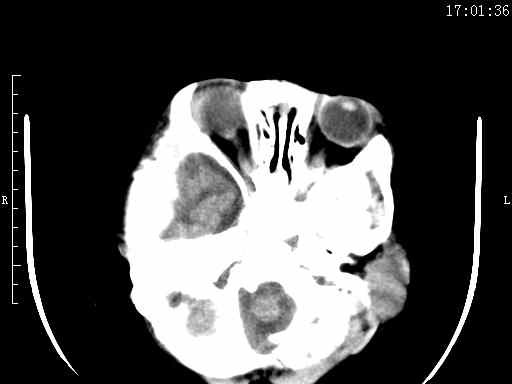

以下是引用余辉在2009-5-30 17:43:00的发言:[br]外围性脑积水在蛛网膜下腔,这个不像,双侧客部液区增宽,内见对称性弧形线状高密度影,边缘清晰锐利,右侧后端终止于冠状缝,左侧终止于人字缝,应该是硬脑膜.双侧硬膜下液区增宽,脑皮质受压变平,脑沟裂无显著增宽,考虑1双侧额颞顶部慢性硬膜外血肿伴硬膜下积液或慢性血肿2双侧慢性硬膜下积液伴硬脑膜剥离并有交通积液(反正考虑硬膜下及硬膜外的慢性血肿或积液)